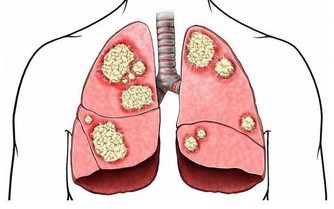

我們通常習慣於把發生在老年人身上的一系列認知障礙叫做老年癡呆。事實上,主要影響65歲以上的人群的癡呆症,有四種常見類型:阿爾茨海默病、路易體癡呆、血管性癡呆和額顳葉癡呆。

額顳葉癡呆是這類癡呆症中比較少見的類型,由於額顳葉萎縮,主要影響大腦的前部和側面,並導致行為和語言問題。與其他類型的癡呆症不同,它往往從較年輕的時候開始,女性患者較多。換句話說,即使你還沒有到60歲,也要注意觀察這種“老年”癡呆的跡象。

額顳葉癡呆的症狀可能包括下面這些內容:

1.人格和行為改變:行為不當或衝動,變得自私或無情,忽視個人衛生,暴飲暴食或失去動力。

2.語言問題:說話很慢,顛三倒四,用詞錯誤,發音不清等。

3.心智能力問題:容易分心,無法制定計劃和組織活動。

額顳葉癡呆的另一個跡像是記憶問題,不過這類問題往往發生在後期,不像更常見的癡呆症如阿爾茨海默病那樣一開始就出現。

另外,患者也可能存在身體方面的問題,比如運動緩慢或身體僵硬,膀胱或腸道控制喪失(通常在晚期出現),肌肉無力或吞嚥困難。